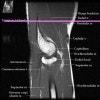

팔꿈치 관절의 MRI 단면 영상

- Sagittal section

1) Biceps Brachii tendon and Brachiallis muscles

2) Radial head for radiographically occult fractures

3) Distal Triceps tendon